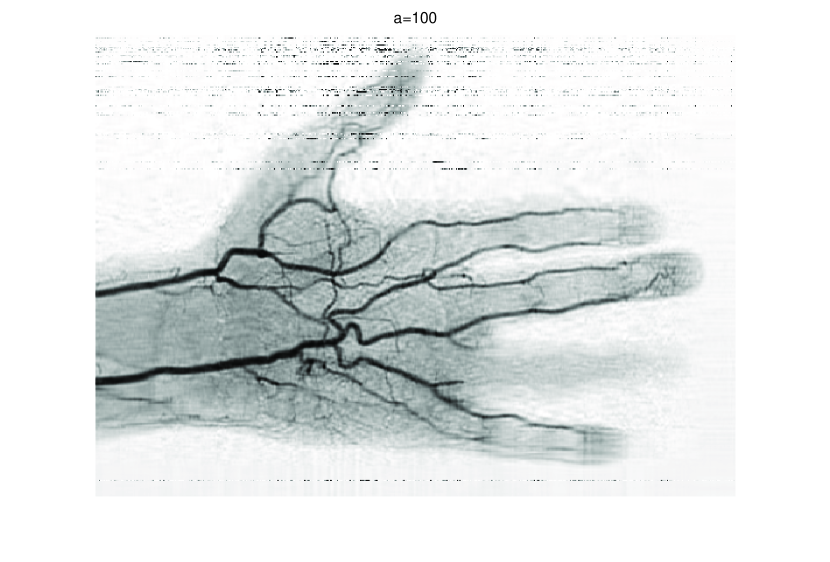

In this subsection, we demonstrate performances of ISVTA on image inpainting problems. The ISVTA is tested on some medical grace images (255×192255192255\times 192 Brain angiography image (BAI), 395×549395549395\times 549 Hand angiography image (HAI) and 419×400419400419\times 400 Intracranial venous image (IVI)). We use the SVD to obtain their approximated low-rank images with rank r=30,40,30𝑟304030r=30,40,30, respectively. Numerical results of ISVTA for theses low-rank image inpainting problems are reported in Table 5, 6, 7, 8.

Table 5, 6 show that ISVTA performs powerful in finding a low-rank matrix on image inpainting problems. Indeed, we could get an exact low-rank image by the ISVTA by choosing proper a𝑎a. Moreover, it is necessary to point out that our method does not work well for all a>0𝑎0a>0, and we can find that a=100𝑎100a=100 is not a good strategy for the low-rank IVI either SR=0.40SR0.40\mathrm{SR}=0.40 or SR=0.50SR0.50\mathrm{SR}=0.50. The numerical results of ISVT, SVTA and SVPA compared in Table 5, 6, 7, 8, 9, 10 under same circumstance show that the ISVT algorithm performs far more better than ISTA and SVPA on image inpainting problems for some proper a>0𝑎0a>0.

Refer to caption

Figure 7: Comparisons of ISVTA, SVTA and SVPA for recovering the approximated low-rank HAI with SR=0.40.